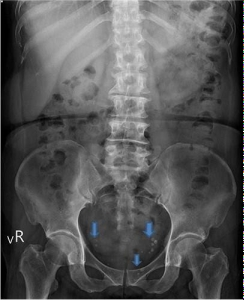

花蓮慈院婦產部婦科主任兼婦科微創手術中心主任龐渂醛表示,臨床上,有些病人可以從腹部X光發現可見鈣化點(藍箭頭白點),這是慢性發炎的證據。